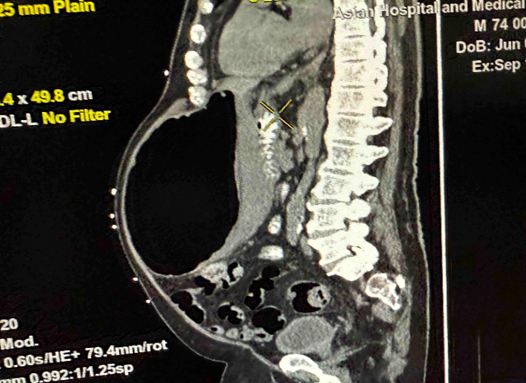

In the above latest admission, his abdominal CT Scan showed gaseous distention of stomach with ill-defined nodular thickening of posterior aspect of the body; the previously noted large lesion in stomach was not clearly demonstrated due to gaseous distended stomach.

Figure 2: a-c: September 17, 2025 Abdominal CT Scan showing previously noted large mass in stomach not clearly demonstrated due to gaseous content.